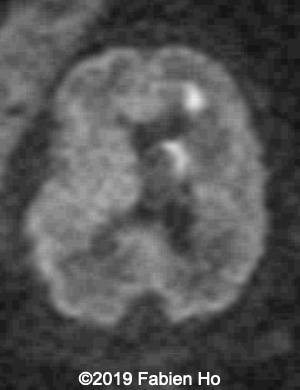

Images 12-16: we performed a second fetal brain MRI at 32 weeks, which showed the same findings as the postnatal neonatal brain MRI as follows:

The evolution of the images is typical of a clastic lesion: after resorption of the ischemic tissue and hematoma, there was now a focal porencephaly with hemosiderin tattooing on its margins. Conversely, persistence of the same MRI findings would have indicated an hypercellular brain tumor, which could have been a differential diagnosis.